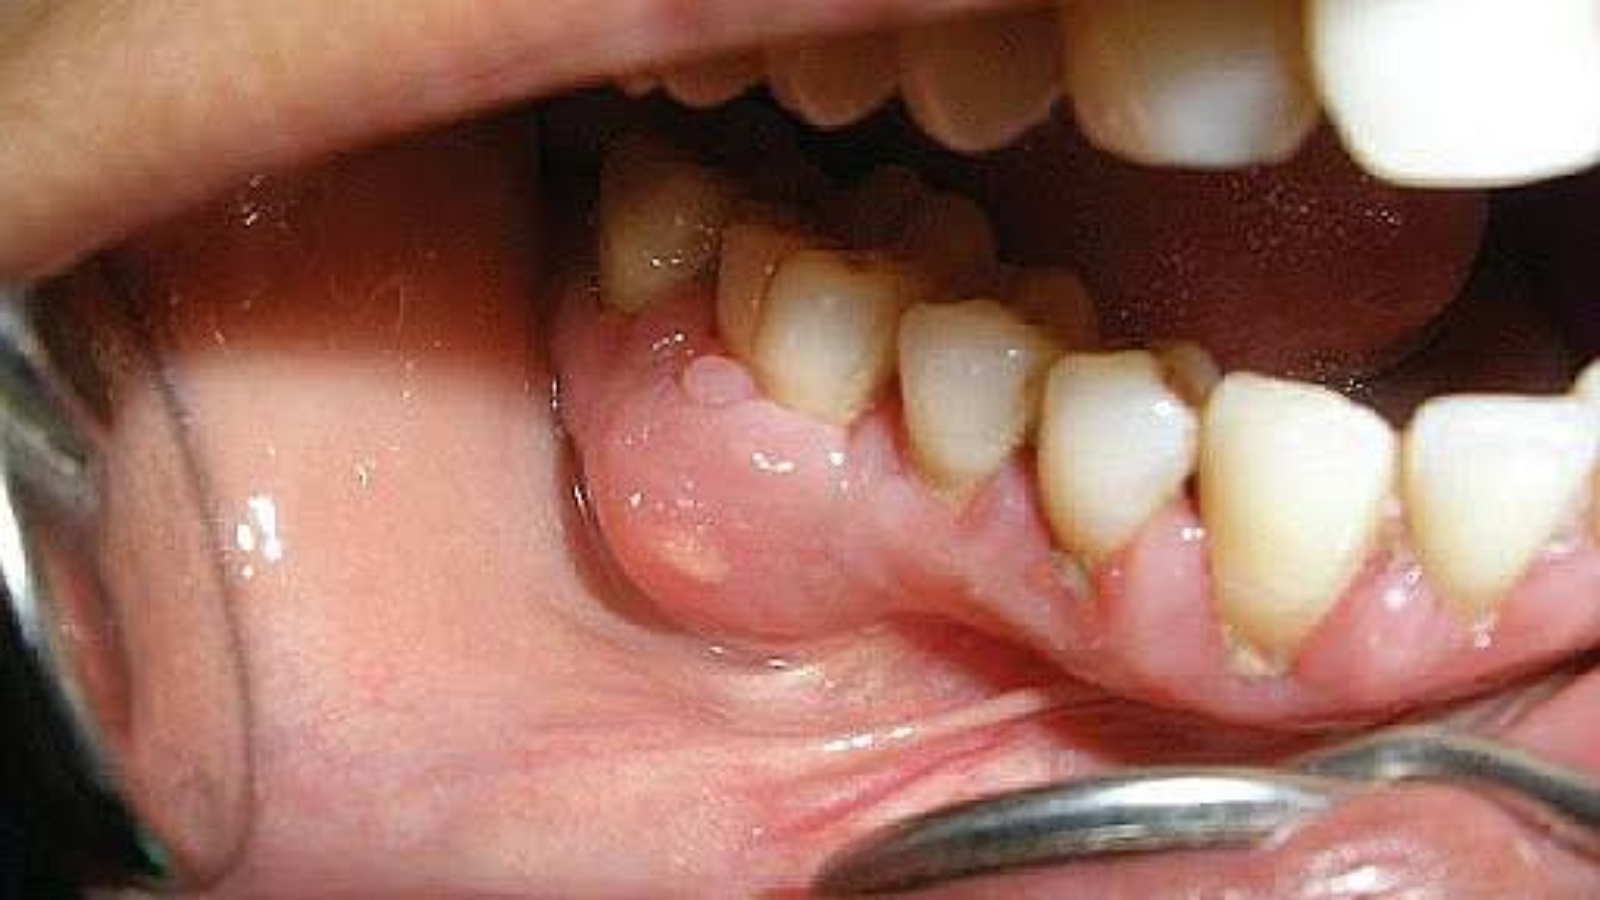

The clinical presentation of periostitis can progress rapidly. Soft tissue swelling, pain on biting, a feeling of pressure, and impaired chewing function indicate increasing tension within the inflamed area. At DentalClinic24, such symptoms are considered an indication for immediate diagnostics, since delay increases the risk of involvement of adjacent anatomical structures.

One of the key risks of periostitis is the spread of inflammation. Without timely treatment, the process may extend to bone tissue, facial soft tissues, or lead to abscess formation. At DentalClinic24, the extent of inflammation is assessed with consideration of jaw anatomy, bone density, and the condition of surrounding structures.